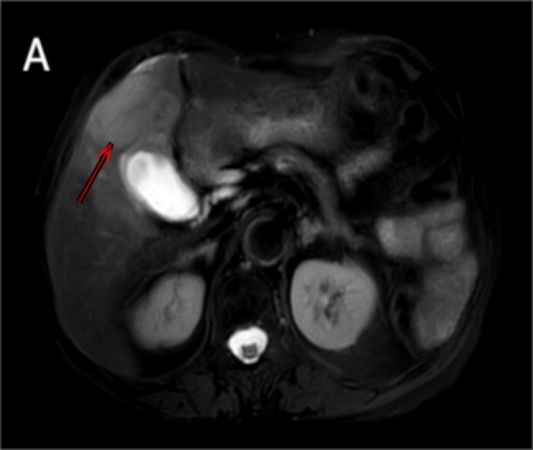

患者女性,80岁,因“右上腹隐痛20天”于2023年11月就诊于当地医院。腹部CT提示肝内占位,遂转至我院进一步诊治。患者否认恶心、呕吐、反酸、黄疸、发热、呕血、黑便等症状。既往有高血压、冠心病及脑梗死病史多年,规律服用降压药及抗血小板药物,病情稳定;无病毒性肝炎、肝硬化或长期饮酒史,家族中无肿瘤遗传倾向。入院查体:生命体征平稳,全身皮肤黏膜无黄染,浅表淋巴结未触及肿大。腹部平坦,未见静脉曲张,右上腹轻度压痛,无反跳痛及肌紧张,肝脾肋下未触及,移动性浊音阴性,肠鸣音正常。实验室检查:肝功能基本正常,直接胆红素9.00 μmol/L,白蛋白39.4 g/L,ALT、AST、ALP、GGT均在参考范围内;凝血功能正常。肿瘤标志物检测结果显示:甲胎蛋白(AFP) 2.0 ng/ml (正常值 < 7 ng/ml),癌胚抗原(CEA) 1.35 ng/ml (正常),糖类抗原CA19~98.75 U/ml (正常);乙型肝炎表面抗原(HBsAg)阴性,丙型肝炎抗体阴性。上腹部增强MRI联合MRCP显示:右肝V段见一大小约4.5 cm × 3.8 cm不规则软组织信号影,T1WI呈低信号,T2WI呈稍高信号,DWI呈明显高信号(图1)。增强扫描动脉期呈轻度不均匀强化,门静脉期及延迟期持续强化,邻近胆囊床受累,局部胆管扩张,胆囊稍增大。未见远处转移征象。初步考虑为肝内胆管细胞癌累及胆囊。经多学科团队(MDT)评估,患者心肺功能可耐受手术,无明确手术禁忌证。行剖腹探查术。术中见肝脏表面光滑,无肝硬化改变;胆囊底部与肝脏结合部有一实性肿块,直径约5 cm,质地坚硬,突出于肝表面,初步判断可能来源于胆囊或肝实质。遂行胆囊切除 + 肝S5段楔形切除术,并清扫肝十二指肠韧带周围淋巴结。术后病理检查示:肿瘤呈结节状,切面灰白、质脆(图2),镜下见大量异型明显的梭形细胞弥漫增生,核分裂象多见,伴有广泛凝固性坏死(图3)。部分区域可见残留腺样结构,提示上皮来源背景。脉管内可见癌栓形成,并见肿瘤侵犯周围神经束。肝切缘及胆总管残端未见肿瘤累及。“胆囊颈”(1/1)及“肝十二指肠韧带旁”(1/6)淋巴结见癌转移。免疫组化结果如下:细胞角蛋白(CK) (+)、CK19 (+)、CD10 (少量+);Hepatocyte (-)、Arginase-1 (-),排除典型肝细胞癌;CD31 (+)、CD34 (-)、ERG (-),排除血管源性肿瘤;Desmin (-),排除平滑肌肉瘤;Ki-67阳性指数约70%,提示极高增殖活性。结合组织形态学与免疫表型,最终诊断为:原发性肝肉瘤样癌(HSC),结节型,低分化,伴脉管癌栓、神经侵犯及区域淋巴结转移(pN1)。

注:A、B、C分别对应T2 SPIR MVXD RT序列、DWI序列、mDIOXN-W序列。

Figure 1. Preoperative MRI images

1. 术前MRI图像

影像学检查在肝肉瘤样癌(hepatic sarcomatoid carcinoma, HSC)的诊断中具有重要价值,常用手段包括CT、MRI及超声。其影像表现受肿瘤大小、生长方式及肉瘤样成分比例等因素影响,缺乏特异性。超声检查中,较小肿瘤多呈低回声,较大者可表现为高回声[6]。CT平扫常显示为边界不清的囊实性低密度灶,增强扫描动脉期多见明显不均匀环形强化,门静脉期及延迟期呈快速廓清,整体强化模式与肝细胞癌相似。值得注意的是,HSC确诊时肿瘤体积通常较大,易侵犯邻近结构。尽管其胆管扩张发生率显著低于肝内胆管细胞癌(intrahepatic cholangiocarcinoma, ICC) [7],这也是本例HSC术前被误诊为ICC的重要原因,但大体积病灶压迫或浸润胆管时仍可引起继发性胆道扩张,导致术前误诊为ICC,本例即因病灶累及胆囊床并伴局部胆管扩张而被初步判断为ICC。MRI表现具有一定特征性:T1加权像多呈低或等信号,T2加权像呈高或稍高信号,DWI序列常呈明显高信号[4]。增强扫描多表现为动脉期周边或不均匀强化,部分病例呈现进行性延迟强化,约1/3病例可见持续性高强化[5];这一现象可能与肿瘤间质纤维化或血供分布相关。另有研究显示,24例HSC患者中多数以“周边强化”为主[4],而另一项17例研究则报告以渐进性强化为特征[5],差异可能源于样本量不同或肿瘤内部肉瘤样成分比例及微血管结构异质性所致。综上所述,HSC的影像学表现多样且非特异,易与其他原发性肝癌混淆。结合临床背景,细致分析其强化模式、病灶形态及伴随征象,有助于提高术前识别能力,但仍需依赖术后病理确诊。

本病例术前被初步诊断为ICC,结合影像学与病理特征分析,误诊原因可归纳为三点。一是影像学征象重叠,患者增强MRI示右肝Ⅴ段病灶呈T1WI低信号、T2WI稍高信号、DWI高信号,增强扫描动脉期轻度不均匀强化,门静脉期及延迟期持续强化,且伴胆囊床受累、局部胆管扩张表现,与ICC典型影像特征高度吻合;尽管文献指出肝肉瘤样癌HSC胆管扩张发生率显著低于ICC [7],但本病例直径约5 cm的较大病灶对胆管形成压迫浸润,继发胆道扩张,与ICC原发胆管受累表现难以区分。二是临床及实验室指标缺乏特异性,患者仅表现为右上腹隐痛,无恶心、呕吐、黄疸等特异症状,AFP、CEA、CA19-9等肿瘤标志物均处于正常范围,肝功能、凝血功能无显著异常,且无病毒性肝炎、肝硬化病史,缺乏指向HSC的特异性临床线索。三是病理特征的复杂性决定术后确诊的必要性,HSC确诊需依赖病理组织学与免疫组化检查,核心特征为同一肿瘤内上皮源性癌与间叶源性肉瘤样成分共存,免疫表型呈“上皮–间叶双表型”;本病例术后病理见大量异型梭形细胞弥漫增生,局部残留腺样结构,免疫组化CK (+)、CK19 (+)提示上皮来源,Hepatocyte (-)、Arginase-1 (-)排除典型肝细胞癌,结合Ki-67阳性指数约70%的高增殖活性确诊为HSC。而ICC以腺管状细胞排列、CK7/CK19/MUC1阳性为病理特征,与HSC存在本质差异,但此类特征仅能通过术后病理明确,术前穿刺活检受取材局限难以精准鉴别,这也是HSC术前误诊率居高不下的根本原因。